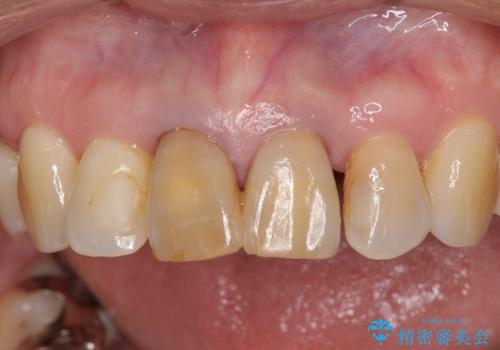

- 上の前歯の変色と、下の前歯のデコボコを気にして来院された患者様です。

前歯はオールセラミッククラウンに補綴することとしました。